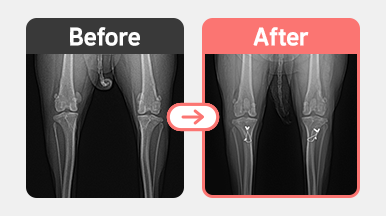

정형센터

치료후기